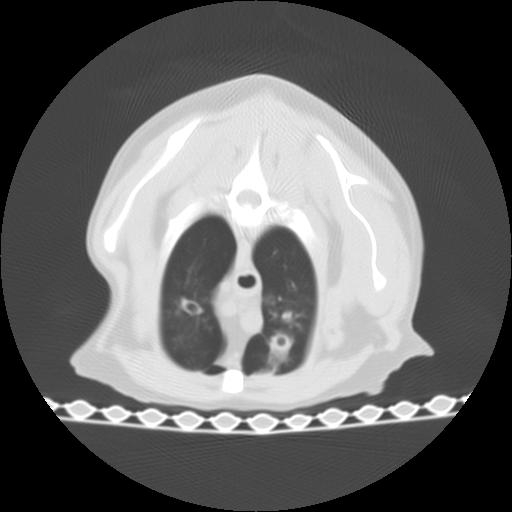

The CT images show that there is severe thickening of the lobar bronchi to the cranial lobes, and also of the proximal portions of the mainstem bronchi. The right cranial lobar bronchus is bronchiectatic, and a large intraluminal soft tissue occlusion is identified peripherally. Multiple other peripheral airways reveal intraluminal soft tissue accumulation. The right middle lobe is collapsed. There are multifocal patchy areas of interstitial and peribronchial infiltrates throughout all lung lobes, but most severe within the caudal lobes.

On the CT images, the right main stem bronchus dilated in periphery in comparison with the opposite side. The conccurent alveolar pattern in X-ray is also confirmed around the heart.